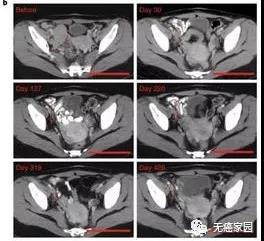

这项早期的临床试验招募26例难治性B细胞淋巴瘤患者,其中25例得到治疗。结果显示,在抗击癌症方面,改良CAR-T疗法表现出色,在低剂量和中等剂量组中,均有一半患者获得临床缓解。而接受最高剂量的11例患者中,6例(54.5%)完全缓解,2例(18%)部分缓解,提示这款经过改良的CAR-T疗法,疗效没有打折扣。

上图为患者的CT图,下图为所有患者的治疗效果统计

这些数据表明,CD19-BBz(86)CAR-T细胞具有强大且持久的抗肿瘤作用。

在研究者更为关注的安全性上,这款新型CAR-T疗法也是表现不俗。在25例患者中,无一例患者出现1级以上的细胞因子释放综合征。更可喜的是,无任何患者出现CAR-T疗法另一常见副作用神经毒性。无一例患者需接受药物治疗来缓解副作用。对比现有获批的CAR-T疗法(超过一半受细胞因子释放综合征困扰,约四分之一有神经毒性),这种新CAR-T疗法初步研究成果令人振奋。